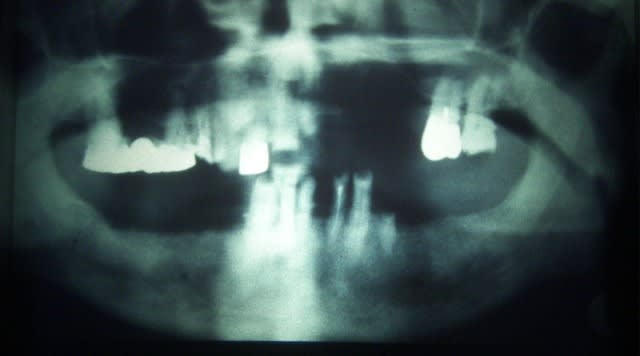

même si j'ai buger le forum ce matin, j'envoies la suite

qui consitait à expliquer à la prothesiste la necessitté de bien dégager les espaces interdentaires (brossettes)